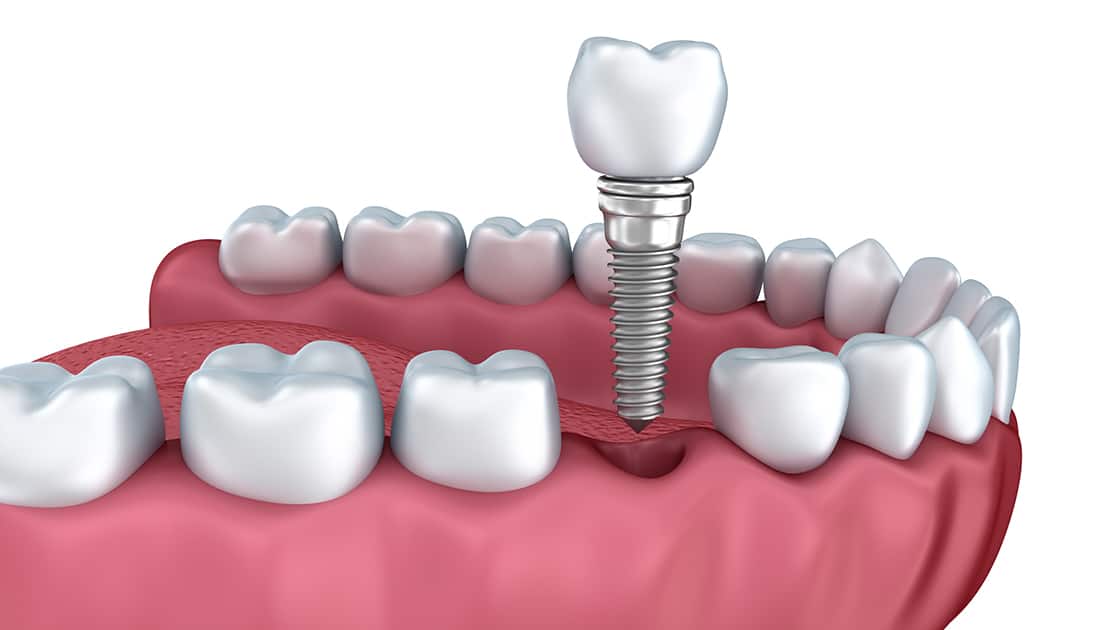

Single Dental Implant

Dental implants are small anchors made of a biocompatible metal called titanium that are placed in the jawbone to replace missing teeth in the mouth. After placement, the anchors will begin to fuse with the bone over the course of a few months. After the fusing process, known as osseointegration, abutment posts are inserted into the anchors to allow for the permanent attachment of the replacement teeth.